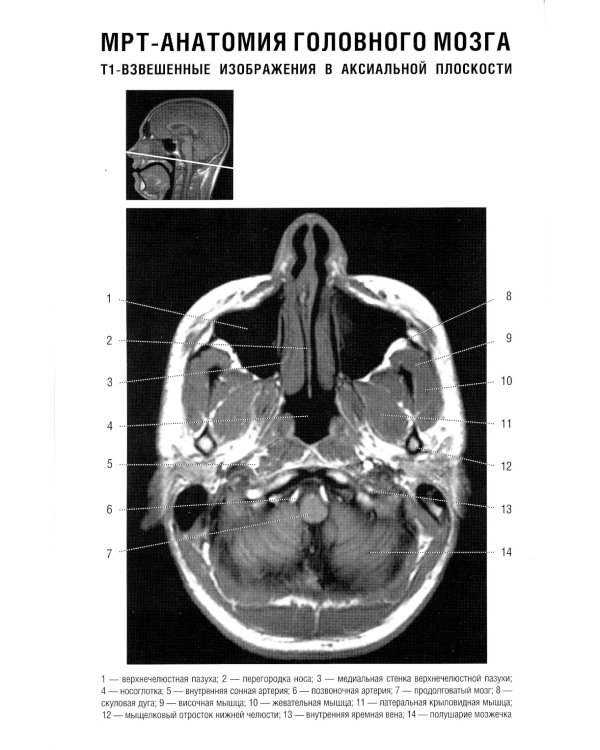

В руководстве представлена нормальная анатомия головного мозга и позвоночника по данным МРТ- и КТ-исследований. MPT-изображения головного мозга отражены в трех взаимно перпендикулярных плоскостях. Отдельная глава посвящена визуализации и нормальной анатомии сосудов головного мозга, в том числе с изображениями, получаемыми при бесконтрастной магнитно-резонансной ангиографии. Для врачей-рентгенологов, специалистов КТ и МРТ, невропатологов, нейрохирургов, а также врачей смежных специальностей. Руководство рекомендовано для обучения студентов медицинских вузов, а также может использоваться в системе последипломного профессионального образования.| Издательство | Элби |